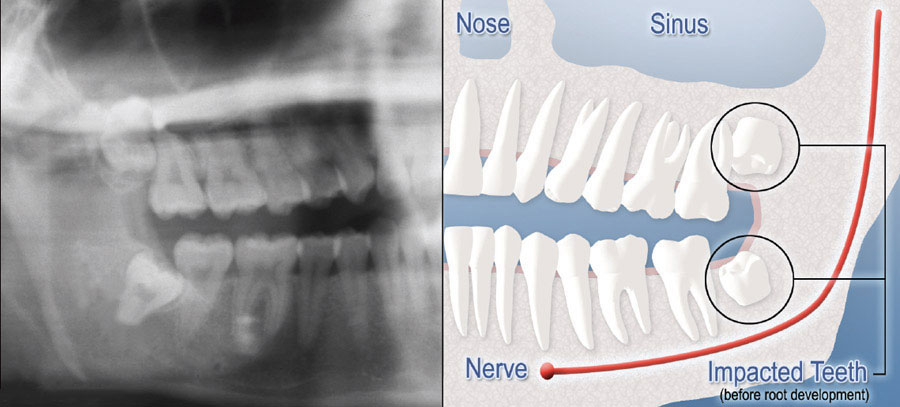

Although most people develop and grow 32 permanent adult teeth, many times their jaws are too small to accommodate the four wisdom teeth. When inadequate space prevents the teeth from erupting they are called impacted. This indicates their inability to erupt into the proper position for chewing and cleaning.

We will need to see you for a consultation to determine if you will benefit from wisdom tooth removal. A special x-ray of your mouth and jaws (panoramic) will be taken to determine if your wisdom teeth are impacted if there is room for them to erupt, and how difficult it will be to have them removed.

If you do not have enough room in your mouth for your third molars to fully erupt, a number of problems can happen. Impacted wisdom teeth should be removed before their root structure is fully developed. In some patients, it is as early as 12 or 13, and in others, it may not be until the early twenties. Problems tend to occur with increasing frequency after the age of 30. Some of the possible problems related to not removing your wisdom teeth include: